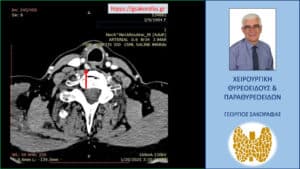

Λόγω επιμένοντος PHPT και με δεδομένους τους περιορισμούς των δύο βασικών διαγνωστικών εξετάσεων (υπερηχογράφημα και σπινθηρογράφημα) παραπέμφθηκε για περαιτέρω έλεγχο με τετραδιάσταση αξονική τομογραφία (4D-CT) όπου περιγράφεται μόρφωμα με διαστάσεις 9 x 7.5 x 5 mm παρά τον οισοφάγο, σε επαφή με την προσπονδυλική περιτονία, στο ύψος του Α6 σπονδύλου, πίσω από την τραχεία και την δεξιά κοινή καρωτίδα.

H εικόνα είναι συμβατή με έκτοπο αδένωμα παραθυρεοειδούς.

Το αδένωμα παραθυρεοειδούς (κόκκινο βέλος) – εγκάρσια διατομή 4D-CT. Βρίσκεται σε επαφή με την προσπονδυλική περιτονία επί τα εκτός και ελαφρά όπισθεν του οισοφάγου (μαύρο βέλος)